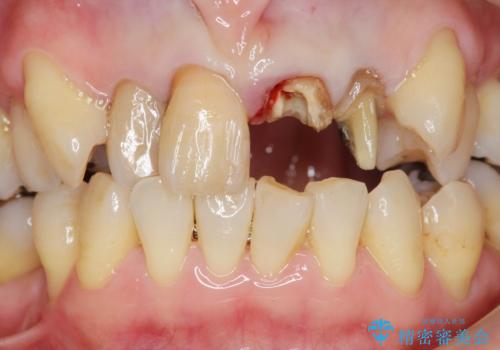

- 前歯のぐらつき、見た目の改善を希望され来院されました。

ぐらつきのある歯は、破折が認められ、その他前歯も不十分な根管治療や不適合なクラウン、レジン修復により審美障害が起きています。

問題を一つづつ丁寧に解決し、前歯の審美性の改善を計画します。

- 52.8万円(ジルコニアクラウン×4・仮歯×4)費用は治療当時の料金となります